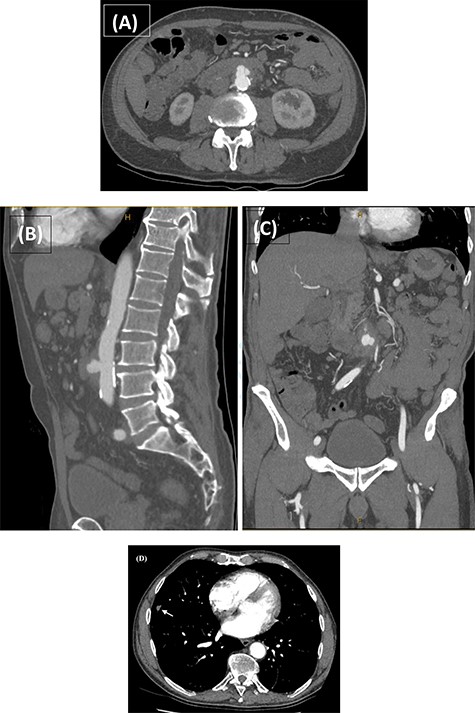

Computed tomography angiography (CTA) confirmed the presence of an infrarenal saccular aneurysm measuring ~35 × 23 × 32mm. Additionally, a right middle lobe pulmonary nodule was noted (Fig. 2), which was further characterized with a high-resolution CT (HRCT) chest. Blood, faecal and urine cultures were negative. Management involved a combination of antibiotic therapy and semi-urgent surgical excision and reconstruction of the infected aorta. Bilateral leg duplex ultrasounds (US) were performed for preoperative planning of an autologous interposition graft using femoral vein (FV), demonstrating no deep venous thrombosis (DVT) and an adequately sized FV measuring 13 mm in diameter.

CTA performed following the MRCP demonstrating the presence of a thick-walled multi-lobulated saccular aneurysm arising from the anterior wall of the infrarenal abdominal aorta approximately at the level of the IMA origin. The aneurysm measures ~35 × 23 × 32 mm with adjacent soft tissue stranding and enlarged nodes in the aortocaval and left para-aortic region (A–C). The incidentally noted right middle lobe nodule is also demonstrated (D; white arrow).